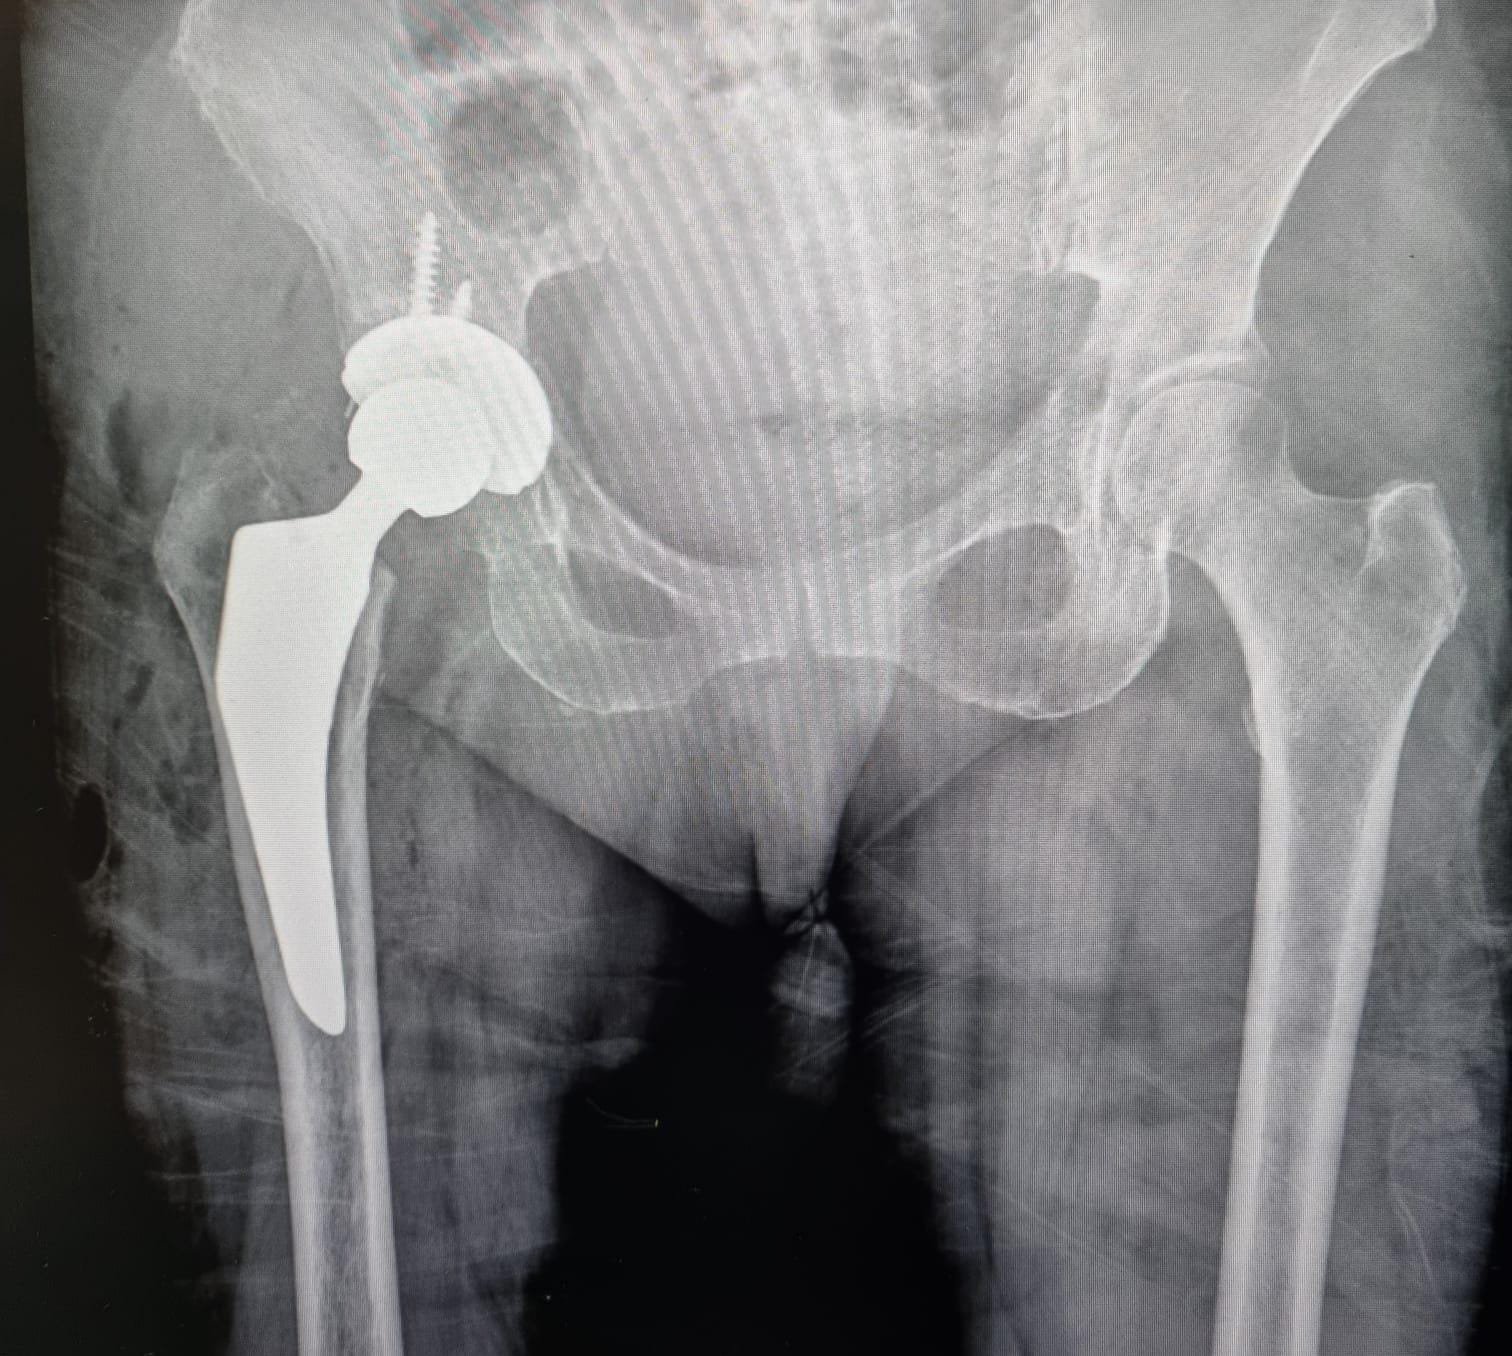

El Dr. José Luis Rodríguez García cuenta con el título de Especialista en Ortopedia y Traumatología.